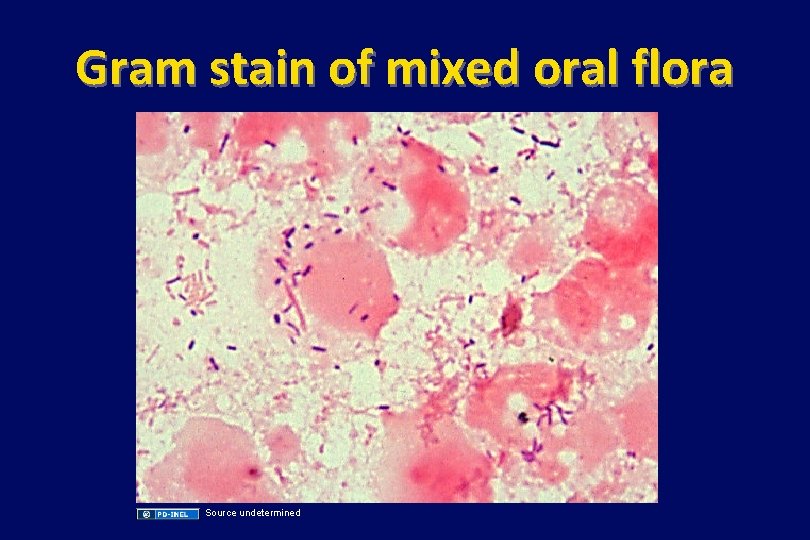

Gram stain of mixed oral flora Source undetermined

Oral, Gram-negative anaerobes • Common pathogens in dental infections, chronic sinusitis, aspiration pneumonia, lung abscesses – Porphyromonas asaccharolytica, gingivalis, forsythus – Prevotella melaninogenicus (named for brown pigment production) • These species are usually (not always) sensitive to clindamycin. PCN+metronidazole usually works well. • Infections are polymicrobial and usually include oral (viridans) streptococci, anaerobic strep, and other oral bacteria.